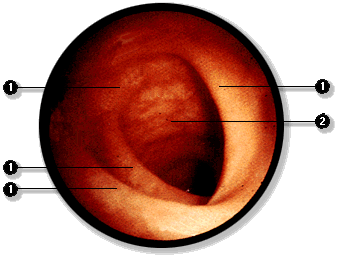

En el sujeto vivo el estómago,

el duodeno y la porción superior del yeyuno puden ser explorados

directamente mediante la técnica de endoscopía.

En este examen se introduce por vía

oral, el fibroscopio, el cual es deslizado a través de la faringe

y esófago hacia el estómago y el instestino. A través

del instrumento es posible realizar cauterizaciones de puntos sangrantes

y tomar muestras de mucosa. El examen que incluye todas estas vísceras:

esófago, estómago, intestino delgado se denomina panendoscopía. |